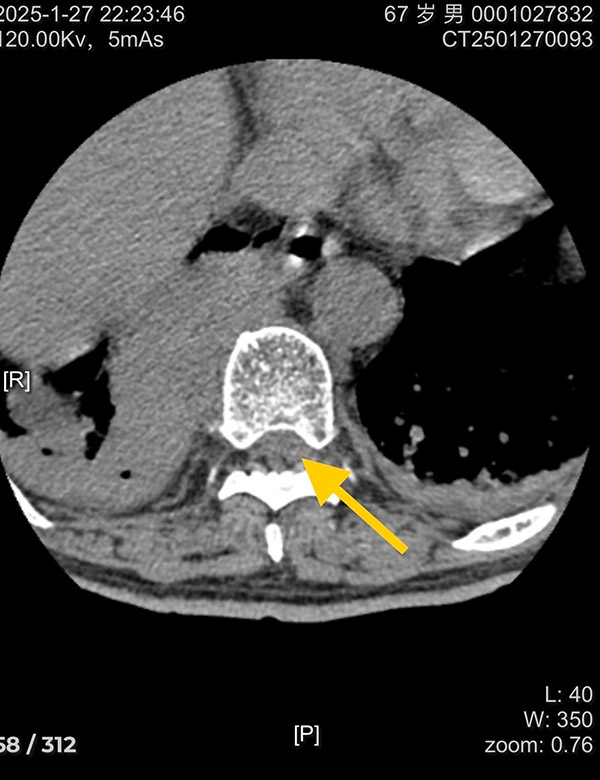

接到紧急通知后,脊柱外科的医生们迅速响应。他们告别了家中热闹的聚餐,告别了正在欢笑玩耍的孩子,告别了翘首以盼的亲人,第一时间赶回医院。此时,无影灯下,一场与时间赛跑的生命救援正式拉开帷幕。 手术台上,医生们全神贯注,每一个操作都精准而谨慎。他们深知,这场手术不仅关乎老人今后的生活质量,更关乎一个家庭的幸福。胸椎9 - 10椎体感染伴全瘫病灶清除减压手术难度极高,但脊柱外科的医护团队凭借着丰富的临床经验、扎实的专业知识和过人的心理素质,沉着应对每一个挑战。他们仔细地清除病灶,小心翼翼地进行减压操作,不放过任何一个可能影响手术效果的细节。 手术室外,老人的家属焦急地等待着,每一分每一秒都显得无比漫长。他们的眼神中充满了担忧和期待,心中默默祈祷着手术能够顺利成功。而医护人员的每一次沟通,都是给家属吃的定心丸,让他们在焦虑中感受到了一丝温暖和希望。 经过数小时的艰苦奋战,手术终于顺利完成。当医生们走出手术室,脸上虽然带着疲惫,但眼神中却透露出欣慰和自豪。他们成功地为老人清除了病灶,减轻了神经压迫,明确病因,为老人重新站起来带来了希望。这一刻,所有的付出都变得无比值得。 在术后的护理过程中,脊柱外科的护理团队时刻关注着老人的生命体征,精心照顾老人的生活起居。无论是按时为老人翻身、换药,还是耐心地安抚老人的情绪,她们都做得细致入微。大年初四早晨,术后第三天,老人的下肢感觉定位觉逐渐恢复,同时通过医院实验室的病原学培养明确为耐药金黄色葡萄球菌感染,为后续治疗指明了方向。随着症状逐渐好转,患者和家属的脸上都露出了久违的笑容。 沈阳市第十人民医院(沈阳市胸科医院)脊柱外科的全体医护人员,用实际行动诠释了医者仁心的深刻内涵。在这个特殊的春节,所有医院工作在一线的医护人员放弃与家人团聚的时光,坚守在救死扶伤的第一线,为患者的生命健康筑起了一道坚固的防线。